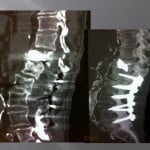

Vertebroplasty technique in the burst fracture of A2 type in the Magerl classification (split-burst fracture)

Vertebroplasty in the split-burst fracture is a delicate intervention for numerous reasons. The fracture separates the vertebral body into two parts with a possible recess of the posterior wall. This intervention stays in the limits of the indications of vertebroplasty, it must be decided in conjunction with the neurosurgical or orthopedic team.

Numerous publications show the efficacy of this procedure (amoretti, huet) and the small rate of complication. In our experience, the coupling of scopy and scanner is fundamental. The axial cuts allow for visualization of the extremities.

The progression of trocars is done successively by controlling the scanners and lateral scopies. We use 13 gauges trocars, the penetration is performed manually, we avoid using a surgical hammer to limit he risks of displacements of bone fragments. We **transfixions the fractured centre with the two trocars bilaterally and symmetrically. , their ends being located medially to limit lateral leaks.

The cement is injected at the level of the anterior fragment of the fracture at its paste phase, then the trocars are slowly withdrawn at the level of the fracture while injecting progressively the cement and create a cement bridge with the anterior fragment and the fracture trait. A scanner control verifies that the end of the trocars is located perfectly in the fracture. The cement is injected slowly in the cannula and pushes with the needle of the trocar.

The lateral scopy controls real time diffusion of the cement in the fracture. The axial scannographic cuts confirm the correct diffusion in the fracture and the absence of para-vertebral leaks. The trocars are progressively withdrawn while injecting cement in the cannula with a needle. Standing up is authorized the day after with wearing corset. The clinical and radiological follow up is rigorous to avoid detecting all neurological sign of compression and appreciate the vertebral consolidation.